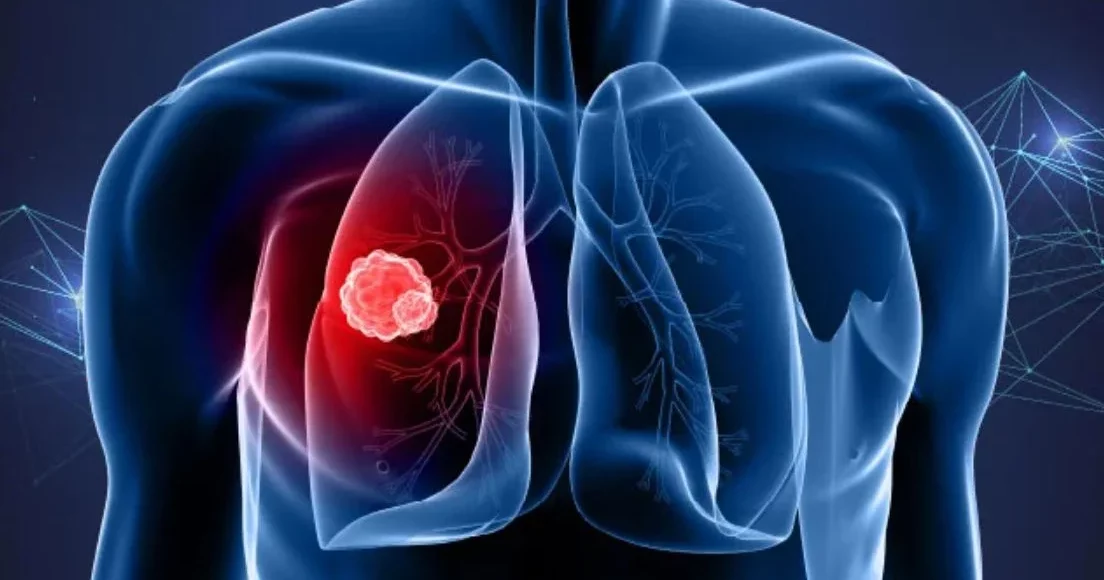

Επιστήμονες από το Πανεπιστήμιο του Gothenburg ισχυρίζονται ότι ανακάλυψαν μια πρωτεΐνη η οποία αυξάνει τον κίνδυνο επέκτασης και επανεμφάνισης του καρκίνου του πνεύμονα μετά τη θεραπεία. Τα αποτελέσματα της έρευνάς τους ίσως σημάνουν πιο στοχευμένες θεραπείες, ιδίως για τους μεγαλύτερους σε ηλικία ασθενείς.

Ειδικότερα, η ομάδα συνέκρινε καρκινικούς όγκους του πνεύμονα από νεαρά και μεγαλύτερης ηλικίας ποντίκια. Ανέλυσαν παράλληλα δεδομένα από 1.000 ασθενείς σε περιοχές της Σουηδίας. Τα αποτελέσματα της έρευνάς τους δημοσιεύονται σε έρευνα στο περιοδικό Nature: DOI: 10.1038/s41586-026-10216-0) και αποκαλύπτουν ένα συνεχιζόμενο μοτίβο.

- Στους μεγαλύτερης ηλικίας ασθενείς, οι όγκοι ήταν μικρότεροι ενώ ο ρυθμός ανάπτυξής τους ήταν πιο μικρός.

- Από την άλλη πλευρά η ασθένεια είχε ήδη εξελιχθεί τη στιγμή της διάγνωσης και επεκταθεί σε άλλα όργανα.

Όπως επισημαίνει ο Volkan Sayin του Πανεπιστήμιο του Gothenburg κάτι τέτοιο εξηγεί με τον πιο χαρακτηριστικό τρόπο ένα παράδοξο που αντιμετωπίζουμε ιδιαίτερα στους μεγαλύτερης ηλικίας ασθενείς, οι οποίοι μπορούν να διαγνωστούν με έναν μικρό καρκινικό όγκο, ο οποίος παρουσιάζει σταδιακή και με μικρό ρυθμό ανάπτυξη, ο οποίος όμως σε κάθε περίπτωση έχει ήδη επεκταθεί πολύ σε άλλα όργανα πέρα από τον πνεύμονα, για παράδειγμα στο συκώτι, στα κόκαλα.

Η μελέτη έδειξε ότι καθώς προχωράει η ηλικία του ατόμου, αλλάζει η βιολογική συμπεριφορά του καρκίνου του πνεύμονα, κάνοντας τους όγκους πιο πιθανό να επεκταθούν. Η επιστημονική ομάδα ανίχνευσε μια πρωτεΐνη γνωστή ως ATF4 που υπό κανονικές συνθήκες βοηθάει στην απόκριση στο stress, βοηθώντας στα κύτταρα να αμύνονται σε διάφορους παράγοντες, όπως η έλλειψη θρεπτικών ουσιών.

Στους ηλικιωμένους όμως ασθενείς αυτή η διαδικασία απόκρισης στο στρες επηρεάζεται από τον όγκο, επιτρέποντας στα καρκινικά κύτταρα να επαναπρογραμματίσουν το μεταβολισμό τους. Μπορεί μεν να μην αναπτύσσεται ταχύτερα, όμως οι αλλαγές αυτές στη μεταβολική δραστηριότητα, τους δίνει τη δυνατότητα να εξαπλωθούν και να σχηματίσουν μεταστάσεις.

Αυτό που διαπίστωσαν ήταν αυξημένα επίπεδα ATF4 στους καρκινικούς όγκους σε μεγαλύτερης ηλικίας ατόμων, όπως και σε ποντίκια. Τα αυξημένα αυτά επίπεδα συνδέθηκαν με μεγαλύτερη πιθανότητα επανεμφάνισης του καρκίνου μετά από χειρουργική επέμβαση, αλλά ταυτόχρονα και με χαμηλότερα ποσοστά επιβίωσης. Οι παρατηρήσεις αυτές έγιναν σε άτομα με πνευμονικό αδενοκαρκίνωμα, έναν από τους πιο συχνούς τύπους καρκίνου του πνεύμονα.

Τα αποτελέσματα δείχνουν ότι η ATF4 δεν αποτελεί μόνο μέρος του μηχανισμού που ευθύνεται για την επέκταση του καρκίνου του πνεύμονα, ωστόσο διαδραματίζει όμως και ρόλο στην επιθετικότητά του, αναφέρει η Clotilde Wiel Associate Professor στο Πανεπιστήμιο του Gothenburg.

Ακριβώς αυτή η συμπεριφορά της ATF4 οδήγησε στην ανακάλυψη μιας νέας στρατηγικής για την αντιμετώπιση του εν λόγω τύπου καρκίνου. Όταν οι ερευνητές μπλόκαραν την ATF4 ή κάποια μεταβολική διεργασία που ελέγχεται από την ATF4, η διασπορά του καρκινικού όγκου στα μεγαλύτερης ηλικίας ποντίκια μειώθηκε σημαντικά.

Η εν λόγω έρευνα δείχνει ότι το πρόβλημα μάλλον οφειλόταν στο γεγονός ότι οι θεραπείες δεν απευθύνονταν σε ανθρώπους που είχαν τις περισσότερες πιθανότητες να επωφεληθούν από αυτήν. Εν ολίγοις, τα αποτελέσματα της έρευνάς μας δείχνουν ότι οι εν λόγω φαρμακευτικές θεραπείες λειτουργούν καλύτερα αν χρησιμοποιηθούν πιο στοχευμένα, για παράδειγμα σε μεγαλύτερης ηλικίας ασθενείς όπου οι καρκινικοί όγκοι δείχνουν υψηλή δραστηριότητα ATF4, αναφέρει η Clotilde Wiel.

Οι περισσότερες θεραπείες, συμπεριλαμβανομένων της χημειοθεραπείας, έχουν σχεδιαστεί για να επιτίθενται σε καρκινικούς όγκους οι οποίοι αναπτύσσονται γρήγορα. Ωστόσο όμως, ο εν λόγω τύπος καρκινικού όγκου που αναφέραμε στο άρθρο μας, αναπτύσσεται πιο αργά σε ηλικιωμένα άτομα. Οι ερευνητές καταλήγουν ότι, με βάση τουλάχιστον τα ευρήματα της έρευνας, θα πρέπει να δοθεί μεγαλύτερη έμφαση στις βιολογικές επιδράσεις της ενηλικίωσης, γιατί αλλάζει ο τρόπος με τον οποίο αναπτύσσονται οι όγκοι.